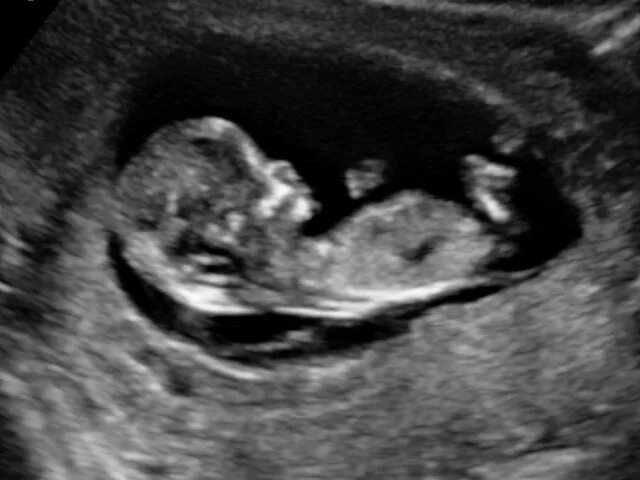

Скрининг 10